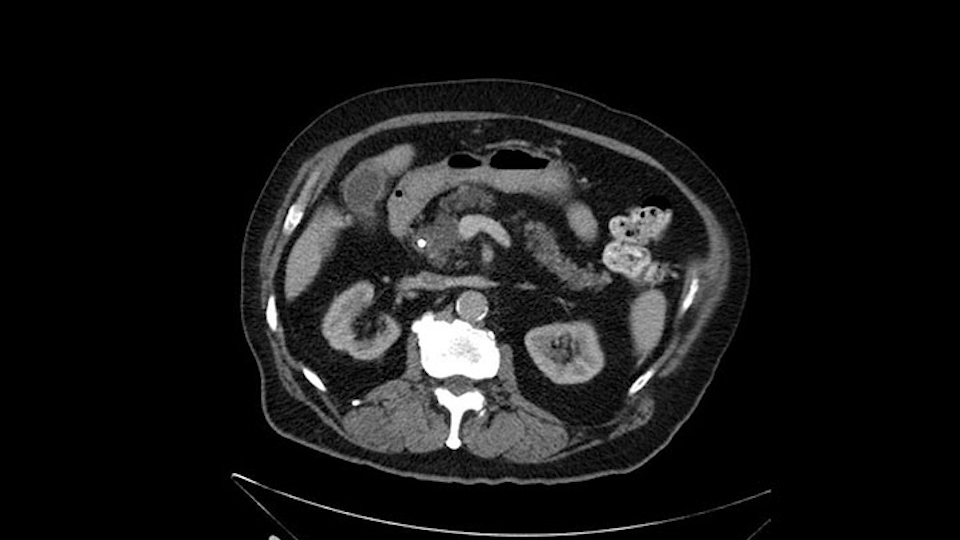

The only difference with him is that he has fairly extensive cystic lesions throughout his pancreas, particularly in the head and the neck. We have thought how this might affect the procedure. Likely IPMN (Intraductal Papillary Mucinous Neoplasms), and we have thought how this might affect the procedure. Is this a pancreatic adenocarcinoma rather than an ampullary cancer? The ampulla (of Vater) was abnormal on a side-viewing scope and a biopsy of this ampulla was adenocarcinoma. So I don’t think this was just a mass invading into the duodenum.

Number two, the reason why I think this IPMN might affect the procedure: it is involving the neck. So normally when we come across the neck, we would like to see a normal pancreas with a small or a large duct but you can see on the scan that this is fairly extensive duct and cystic lesion at that point. The only slowing down moment for me is really that. Coming across the pancreas, then wanting to see what that looks like and how that is going to affect my anastomosis.

Anyhow. What the surgeon does need to do though, is focus on the resection. What I generally do is look at the tumor, which is here, and then I look at the nature of the pancreas. That’s really just to get an idea on what it would be like to do the pancreatic anastomosis, which isn’t technically the biggest deal, but it’s the biggest deal for the patient afterwards; and the larger the duct and the harder the pancreas, the less likely it’s going to leak. Leaks are what cause almost all the morbidity so I do think of it mentally. I wouldn’t do anything differently, the night before or the morning or the surgery or during the surgery, but certainly mentally it’s useful to know that you may have a challenge in terms of doing the best pancreatic anastomosis you can. I think the duct is quite large. The interesting thing about the duct: it does peter out into fairly normal looking pancreas; that’s a bit strange. But I’ll assume the duct is large.

I see a dilated biliary system but I also see a dilated pancreatic ductal system which is almost looking cystic in the head and neck region of the body. When I tackle the neck of the pancreas during the course of the surgery, I would have to pay particular attention to the neck of the pancreas when I transect it, to see for any changes of associated IPMN. They may not be IPMN but the thing is there is dilatation and that’s why I need to be careful, with the consideration for intraoperative frozen section for the pancreatic neck margin.

When reviewing the images of this patient, it is striking that there is a large dilation of the Wirsung duct, which is unusual in patients with carcinoma of the ampulla of Vater, and the dilatation in the head of the pancreas has almost replaced all the parenchyma, therefore there is a significant suspicion that the patient has an intraductal papillary mucinous tumor of the pancreas. It’s possible that it's a result of the same pathology and what we are seeing at the ampulla of Vater is the protrusion - because the pancreatic ducts are full of mucus; but we have a biopsy of adenocarcinoma, which could be a malignant degeneration, of an intraductal papillary mucinous tumor or a coincidence pathology, in addition to adenocarcinoma of the ampulla of Vater. Either way, if this patient is having surgery, the decision would be a pancreatoduodenectomy, But we should consider the possibility that the patient might have a intraductal papillary mucinous tumor of the pancreas.

I've been asked to look at the images and talk about the care of a patient who has a biopsy proven ampullary carcinoma. But he also has some interesting changes involving the proximal main pancreatic duct, which certainly could be consistent with a main duct IPMN involving the duct.

There is a bit of a challenge in my mind that will have to be determined intraoperatively and that's the extent of the pancreatic duct dilatation as you move from the head of the gland more distally into the body and tail. We certainly can see dilatation of the pancreatic duct in patients with ampullary carcinoma. But this seems a little bit unusual in terms of the extended dilatation. It also stops pretty dramatically at the body of the gland with the dilatation not extending to the tail. So again, raises the suspicion that this could be a main duct IPMN. The patient would not require any further preoperative imaging. I don't believe an endoscopic ultrasound is going to add anything to this patient's management. So I would take the patient to the operating room at this time. I would not perform a diagnostic laparoscopy, that's not my practice even for pancreatic cancers at least involving the head of the gland.